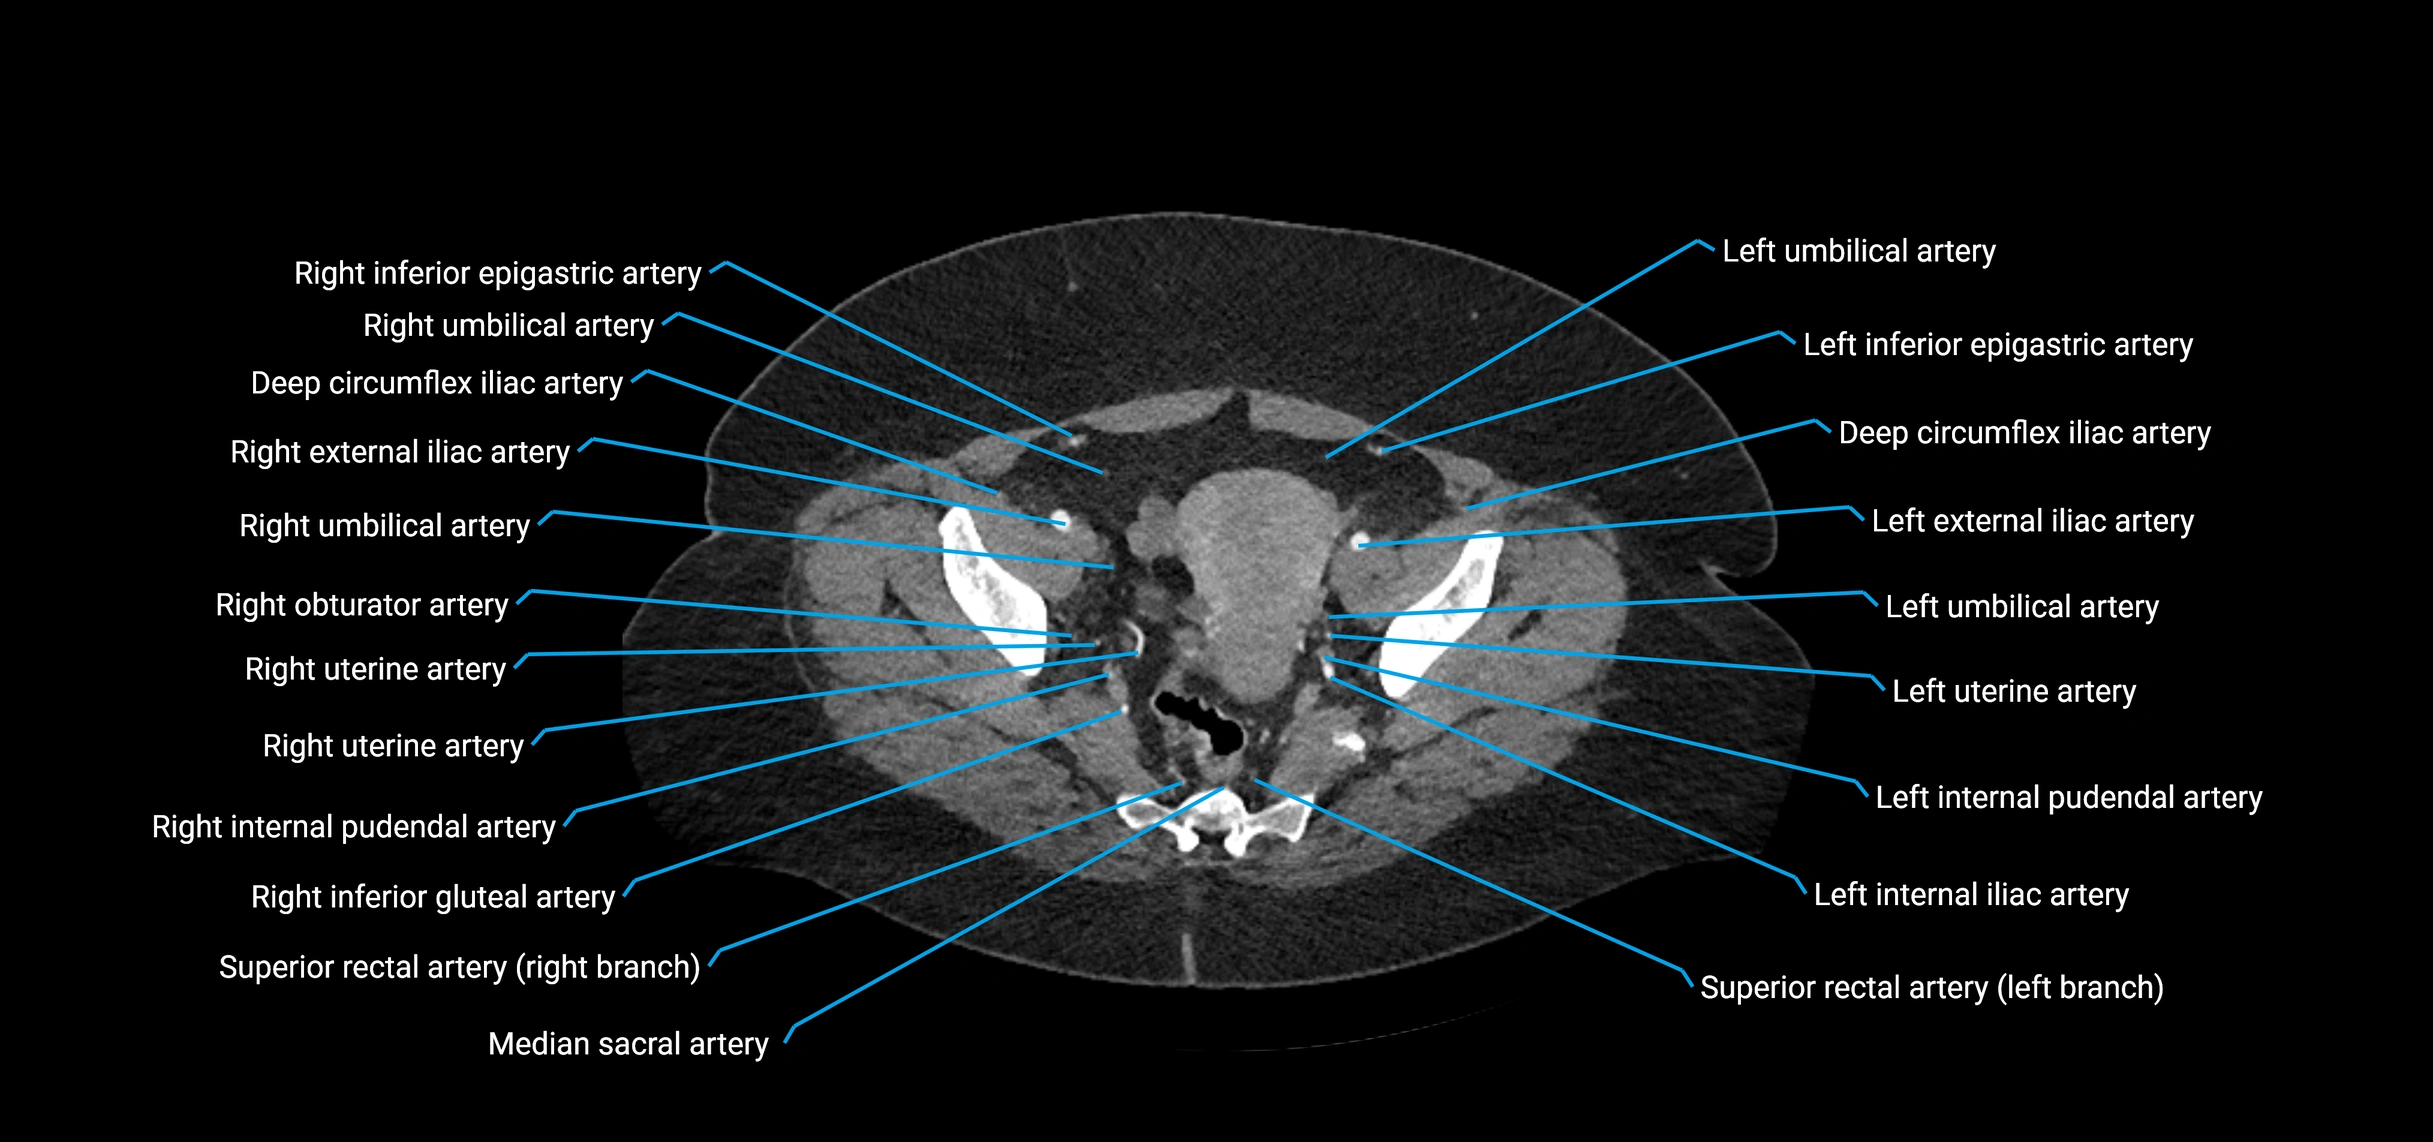

The abdominal aorta is the continuation of the thoracic aorta, beginning at the level of the aortic hiatus of the diaphragm (T12 vertebra) and terminating at the level of the L4 vertebra where it bifurcates into the right and left common iliac arteries. It lies slightly to the left of the midline and courses anterior to the vertebral bodies, surrounded by the retroperitoneal structures of the abdomen.

The abdominal aorta gives off numerous visceral and parietal branches, supplying the abdominal organs, pelvic structures, and lower limbs. It is the main conduit of oxygenated blood from the heart to the abdomen and lower body. The aorta is clinically significant as the common site of aneurysm, dissection, atherosclerosis, and traumatic injury.

Branches

• Unpaired visceral branches: celiac trunk, superior mesenteric artery (SMA), inferior mesenteric artery (IMA)

• Paired visceral branches: middle suprarenal arteries, renal arteries, gonadal arteries (testicular or ovarian)

• Parietal branches: inferior phrenic arteries, lumbar arteries, median sacral artery

• Terminal branches: right and left common iliac arteries

CT Appearance

Contrast-enhanced CT (CTA):

• Gold standard for abdominal aortic imaging

• Provides excellent detail of lumen, wall, aneurysm, thrombus, and branch vessels

• Multiplanar and 3D reconstructions help in aneurysm measurement, stent graft planning, and dissection evaluation

• Detects acute rupture, traumatic injury, or occlusion with high sensitivity